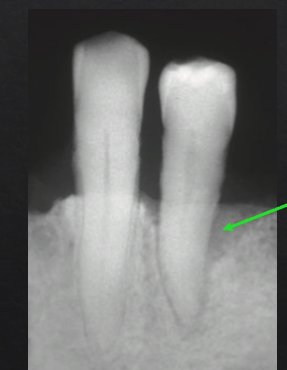

what are the numbers

resorption of collagen, bone, cementum

widened PDL

increased mobility

no attachment loss